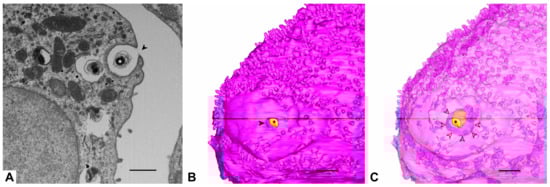

2.1. Generation of the Data Set for 3D Reconstructions

2.2. Segmentation and 3D Reconstructions